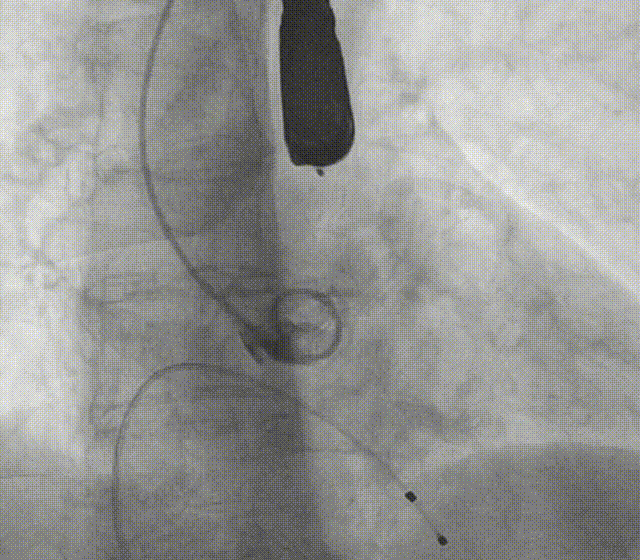

全麻下建立双侧股动脉入路,以右股动脉为主;导丝跨瓣后置换猪尾导管,确定共平面。

图片

使用20mm球囊进行预扩。

通过支撑导丝,送入23mm SAPIEN 3瓣膜,使用独特调弯功能,保证安全过弓并成功跨瓣;调整至共平面角度,瓣膜到位,快速起搏下-2cc精准释放瓣膜。